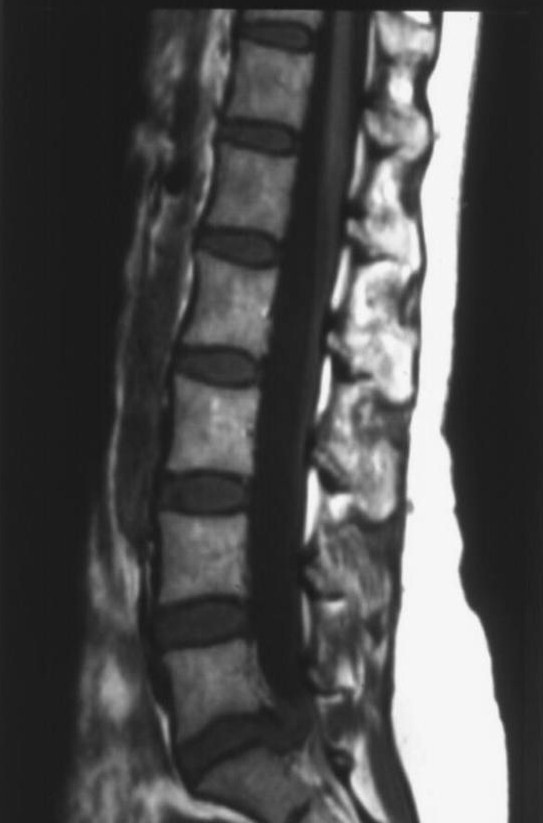

MRI scans are particularly useful for imaging the brain and the musculoskeletal system (e.g. spine and knees) but can also be used to image the arteries when the technique is then called MRA or Magnetic Resonance Angiography. Apart from supervising and reporting scans the role of radiologists like Dr. Crowe is also to advise patients, general practitioners and other specialists which type of scan (ultrasound, CT or MRI) is best to answer the particular clinical concern at the time. MRI scanning is very safe but there are certain exclusions on safety grounds, particularly that individuals with cardiac pacemakers should not go into an MRI scanner.